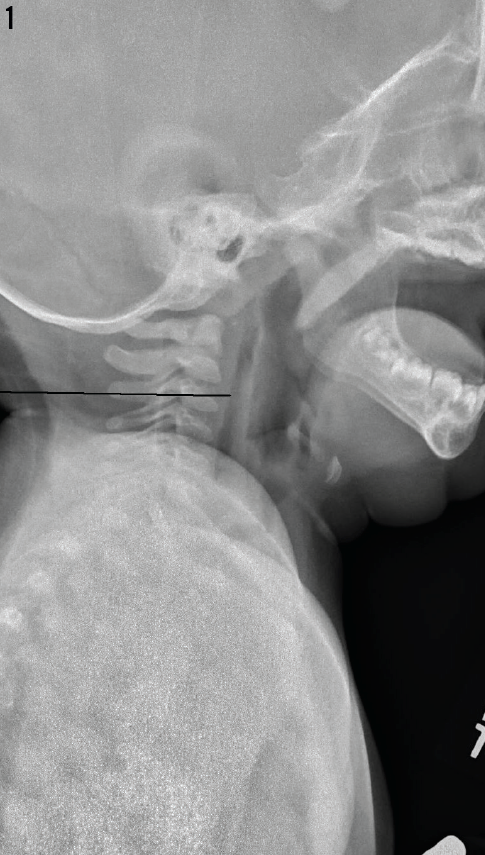

The lateral radiograph taken at the outside hospital is shown in Figure 1.

Lateral neck radiographs (Figure 1) taken at the outside hospital showed no foreign body, but the presence of a column of retropharyngeal air was concerning. Contrast computed tomography (CT) scans of the neck (Figures 2 and 3) and chest confirmed air tracking from the retropharyngeal space, through the chest, and into the mediastinum. Although the source of the air was unclear, this presentation has been seen in cases of perforation of the pharynx. Intravenous ampicillin-sulbactam was started for empiric coverage of aerobes and anaerobes to prevent mediastinitis in the context of likely perforation. Oral food and fluids were withheld.